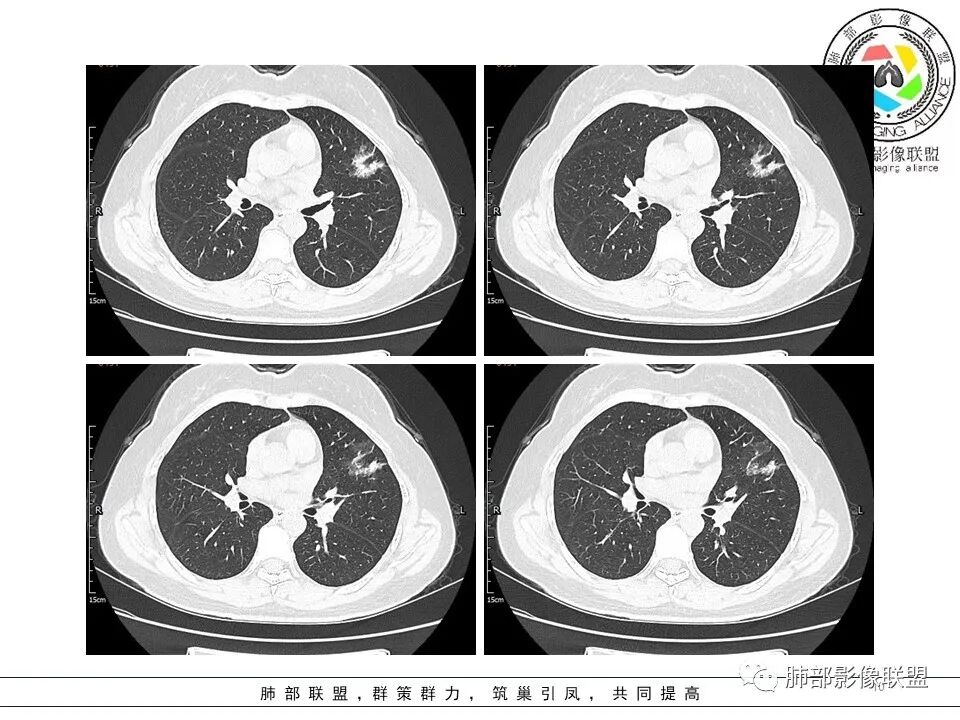

两个结节,大的IAC,小的AIS或MIA,不太有信心的是读片病例往往出乎意料。

左肺上叶近胸膜下磨玻璃小结节,考虑早期腺癌,大结节感觉密度混杂,考虑良性感染

左肺上叶ggo,短毛刺,空泡征,6个月后复查病灶似变大,有轻度不均质强化,腺癌?胸膜下粟粒结节,无变化,良性?

中年女性,发现肺部结节半年,CT左肺上叶磨实混合型结节影,有膨隆,有凹陷,有毛刺,不均匀轻度强化,考虑腺癌可能,鉴别炎肌母

左肺上叶舌段mGGO,实变区可见支气管充气征直达远端并扩张,实变区膨胀与收缩共存,增强轻度强化,血管漂浮,未见受侵,纵隔内未见肿大淋巴结,中年女性,慢性病程,症状逍遥,半年复查病灶增大,倾向恶性病变,高度怀疑MALT。

左上肺实性占位,部分磨玻璃样改变,多发细小毛刺,胸膜牵拉,临近病灶血管增粗,病灶内见支气管,考虑恶性可能性大。鉴别肉芽肿性炎(病灶太散了,病灶中间见正常肺组织,感觉不符合)。

左肺上叶胸膜下结节,边缘可见毛刺及长索条,内可见支气管影略扩张,周围可见片状磨玻璃,增强后呈不均匀强化,内血管略增粗,复查大小没有变化,考虑腺癌。

短毛刺,空泡蜂窝,肺腺癌,靠近胸膜结节太小,性质待定。

中年女性,左肺上叶混合ggo,边界清晰,边缘分叶,内见空泡,短毛刺,血管穿行,胸膜牵拉,增强轻中度强化,考虑腺癌iac。鉴别支气管扩张,扭曲,淋巴瘤

左肺上叶胸膜下实性结节,周围散在磨玻璃结节,边缘收缩,胸膜牵拉,形态不规则,有分叶,毛刺,兔耳征,内部可见多个小空泡,平扫密实尚均匀,增强后不均匀强化,内部可见低密度坏死,血管束穿行,考虑恶性:浸润性腺癌,鉴别炎性肉芽肿。

左肺上叶胸膜下混合密度结节影,其内可见小空泡、扩张支气管,边缘短毛刺、微分叶,周围磨玻璃影,边界清。复查实性成分增多,结节增大,不均匀强化,可见低密度坏死,考虑恶性,腺癌可能

左肺上叶见磨玻璃结节影,部分实变,边缘不规则,可见长短不一毛刺,分叶及胸膜牵拉,病灶内见支气管走形,增强扫描,病灶实变区轻度强化,似见坏死区,考虑腺癌可能。

左肺上叶实性结节分叶短毛刺、细支气管轻度扩张并空泡、周围不规则分叶边界清楚GGO,半年后复查,目测大小没有明显变化,其内的考虑细支气管扩张及空泡变小,说明病灶仍在发展,与胸膜相连,但胸膜凹陷不明显,总体考虑恶性可能,腺癌或粘液腺癌可能,

左肺上叶混合磨玻璃结节,周围可见毛刺,胸膜牵拉,病灶内血管增粗,支气管略扩张,收缩力较大。考虑中分化腺癌;鉴别主要还是感染。

左肺上叶胸膜下混合密度结节影,部分边缘可见磨玻璃,其内可见小空泡,边缘短毛刺、微分叶,不均匀强化,可见低密度坏死,考虑恶性,浸润性腺癌

左肺上叶胸膜下混合磨玻璃结节,实性为主,周围磨玻璃清晰,小空泡,血管进入无破坏,短毛刺,半年复查实性区似稍增大,考虑恶性,腺癌IAC,读片带个尾巴,淋巴瘤代排

有腺癌的影像表现,有半年的无症状结节史,有抗炎无效史(排除普通炎性感染),且半年结节无明显变化(如果是结核或隐球,这样的病灶半年是会变化的,形,态,部位都会变化)。除了IAC,其他可能真的太小了。